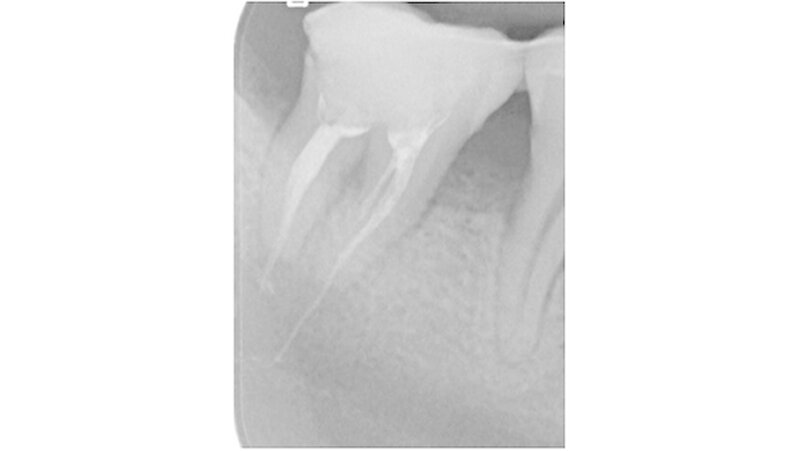

Die dreidimensionale Darstellung des Unterkiefers rechts mittels digitaler Volumentomografie (DVT, Abbildung 4) vervollständigte den Nachweis von röntgenopakem Material im Bereich der Wurzelspitzen des Zahnes 47 mit direktem Kontakt zum Nervus alveolaris inferior. Die Rücksprache mit dem ausländischen Behandler ergab die Information, dass es sich bei dem Füllmaterial um Guttapercha zusammen mit einem paraformaldehydhaltigen Zement handelte.

Nach ausführlicher Aufklärung der Patientin über den Befund erfolgte die Extraktion des Zahnes 47 (Abbildung 5) sowie unter dem Operationsmikroskop die vollständige Entfernung von Wurzelfüllmaterial und residualen Sealerbestandteilen aus dem Nerven und dem Canalis mandibularis rechts. Der durch die Reinigung eröffnete Nervus alveolaris inferior wurde mit resorbierbaren, polyfilen Nähten rekonstruiert und anschließend mit einer porcinen Kollagenmembran zum Schutz ummantelt (Abbildungen 6 und 7).